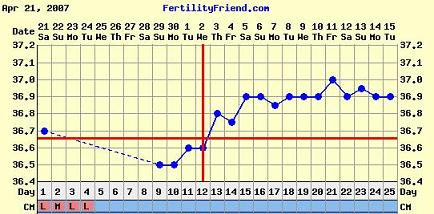

Bettike, tök jó végre tőled egy ilyen szép görbét látni a hiperciklusaid után!

És nagyon simogattyajakicsiszivemet, hogy az én babás görbém ilyen példaértékű. Úgyhogy Bonikám, tiád a pálya, úgyis utálom, hogy mindig az én hsz-om az utolsó a másik hőmérősben.